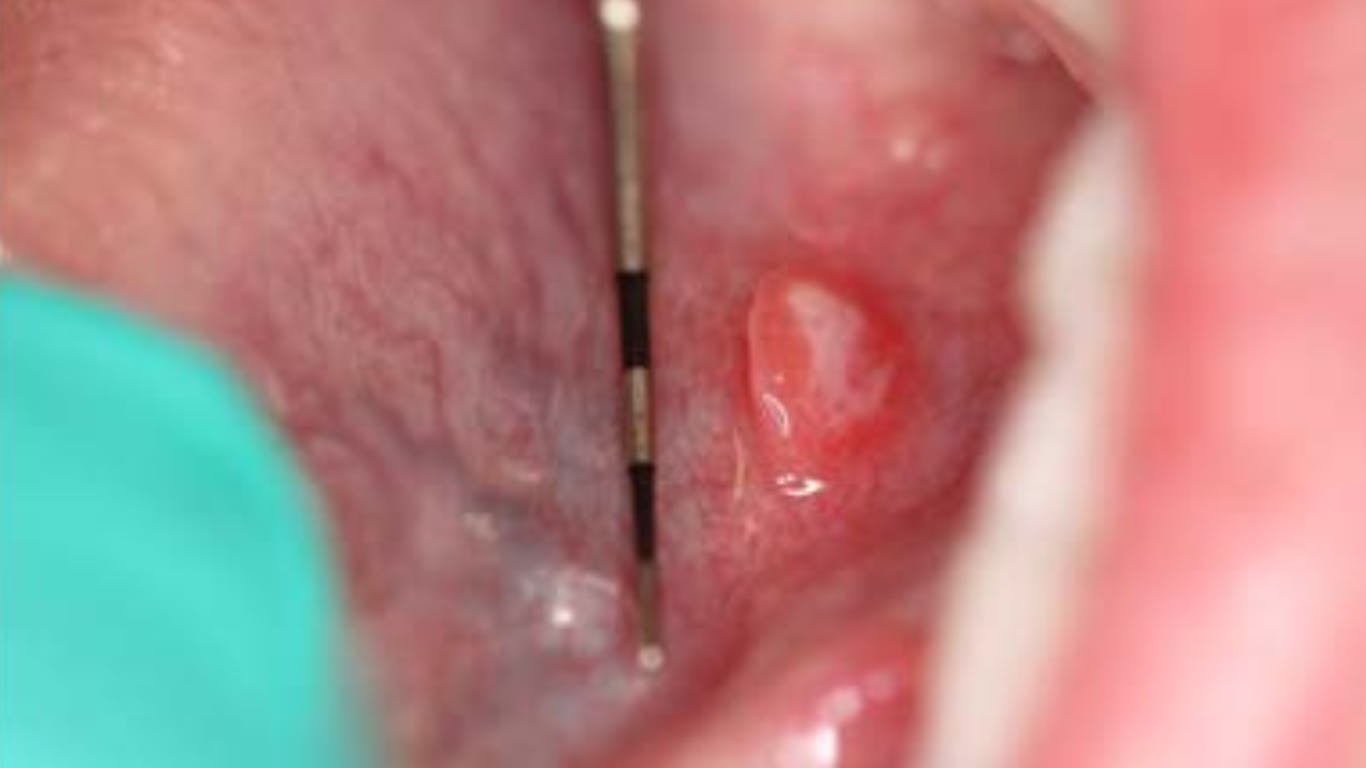

While performing the head, neck, and oral cancer screening exam, a raised, round soft-tissue lesion approximately 6 mm x 6 mm was observed under the left side of the tongue along the sublingual salivary gland ducts. The outside border was red and contained a white center. The lesion and area in general were not tender to palpation, and both mom and patient were unaware of its presence.

Definitive diagnosis: Aphthous ulcer (minor)

Apthus ulcers (minor) are “small superficial ulcers of the oral gland-bearing mucosa that occur episodically in clusters of one to five lesions.”1 It is the most common type of aphthous ulcer found.2 The lesions occur throughout the mouth, including the soft palate, floor of mouth, tongue, mucobuccal fold, buccal mucosa, lips, and movable mucosa (nonkeratinized).2